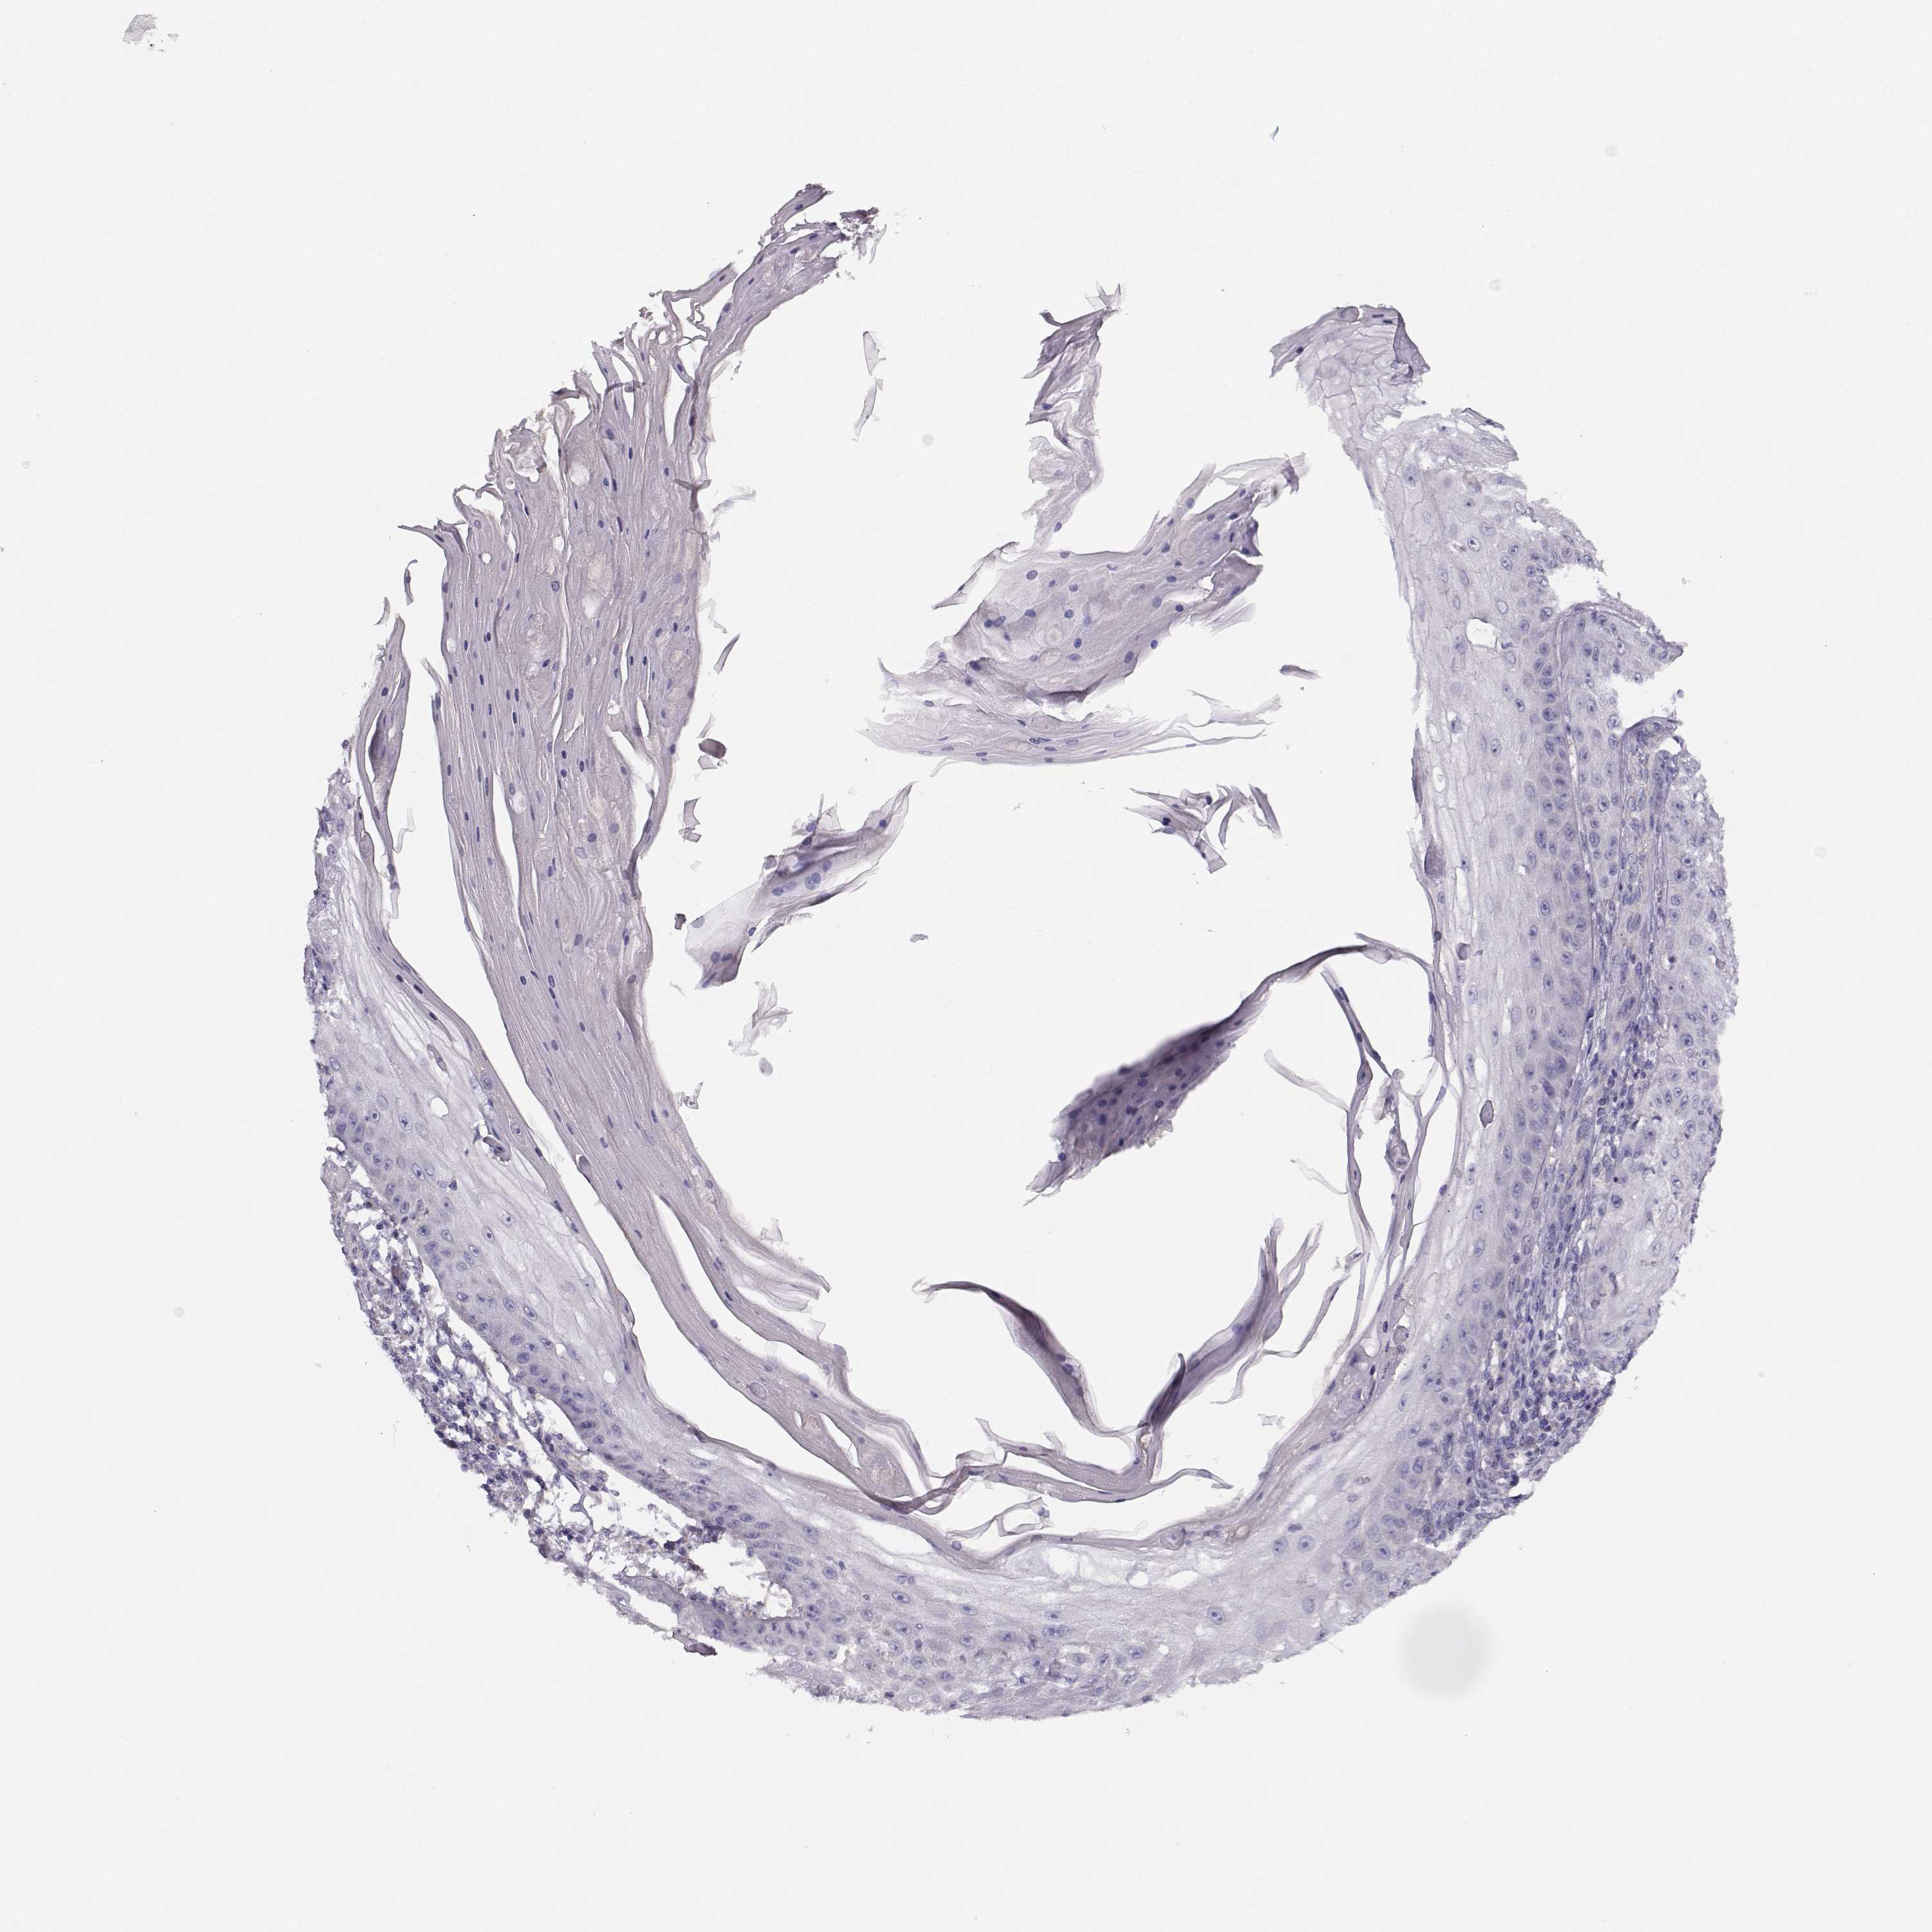

Basal cell and squamous cell cancer

SKIN CANCER - Protein expressioni

A mouse-over function shows sample information and annotation data. Click on an image to view it in a full screen mode. Samples can be filtered based on level of antibody staining by selecting one or several of the following categories: high, medium, low and not detected. The assay and annotation is described here.

Each image is clickable and will lead to virtual microscopy that enables deeper exploration of all samples and also displays staining intensity scores, fraction scores and subcellular localization as well as patient and tissue information for each sample.

Antibody HPA073303

Squamous cell carcinoma, NOS